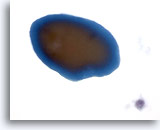

Zeer waarschijnlijk benigne

In deze categorie vallen die folliculaire laesies die een macrofolliculair of gemengd micro- en macrofolliculair patroon vertonen met weinig tot overvloedig colloïde op de achtergrond. Op ThinPrep zijn macrofollikels te zien als lagen van tientallen gelijkmatig verdeelde folliculaire cellen met een goede afstand tussen kernen. De significantie van losse folliculaire cellen op ThinPrep in onzeker, omdat deze worden waargenomen in een verder micro- of macrofolliculair patroon. Omdat de waarschijnlijkheid dat deze laesies maligniteit vertonen (folliculaire variant van papillair carcinoom of folliculair carcinoom) bij histologie laag is, maar niet helemaal nul (in de literatuur varieert het percentage van 0 tot 43%) [6, 9, 12, 13, 14, 15, 16, 17, 18, 19, 20, 21, 24, 25, 26, 27] waarbij op drie na[14, 16, 27] alle studies minder dan 6% rapporteerden, noemen we dit daarom zeer waarschijnlijk benigne in plaats van onmiskenbaar benigne.